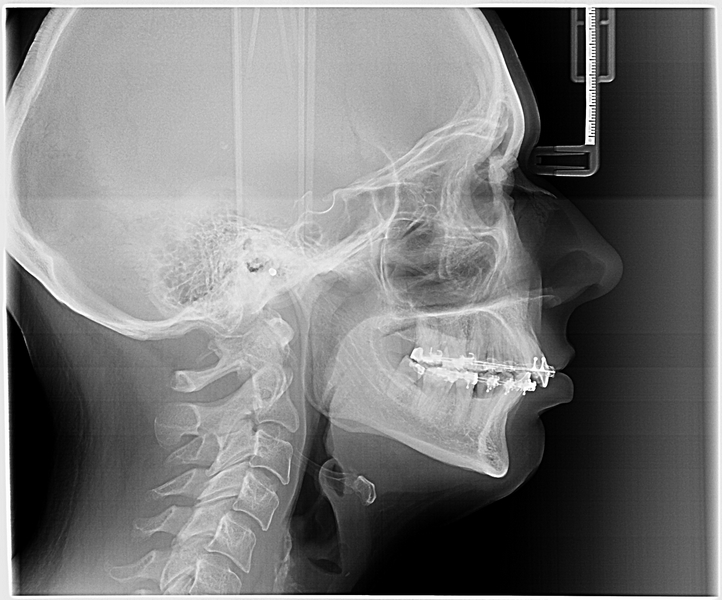

Contrairement aux implants traditionnels qui s’ancrent dans l’os de la mâchoire, ces implants plus longs se fixent directement dans l’os zygomatique, c’est-à-dire l’os des pommettes. Cette zone présente une densité osseuse suffisante et stable qui ne se résorbe pas, même après la perte des dents. L’intervention se déroule sous anesthésie générale et permet généralement de poser une prothèse provisoire dans les 24 à 48 heures suivant l’opération. Le taux de perte de ces implants reste très faible, entre 1 et 2% selon les études récentes.

Une consultation spécialisée en implantologie permettra d’examiner toutes les options possibles grâce à une imagerie 3D et un bilan complet. Chaque technique présente ses avantages et ses limites qu’il convient de peser soigneusement avant de prendre une décision. L’essentiel reste de retrouver une fonction masticatoire correcte et un sourire dans lequel vous vous sentez à l’aise, quelle que soit la méthode choisie.